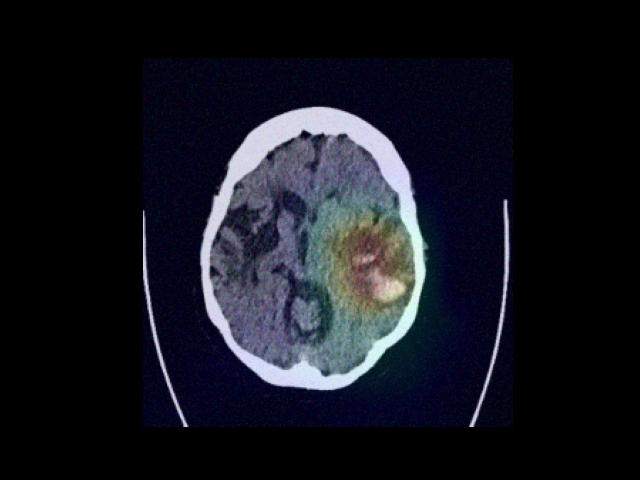

Sample Gallery